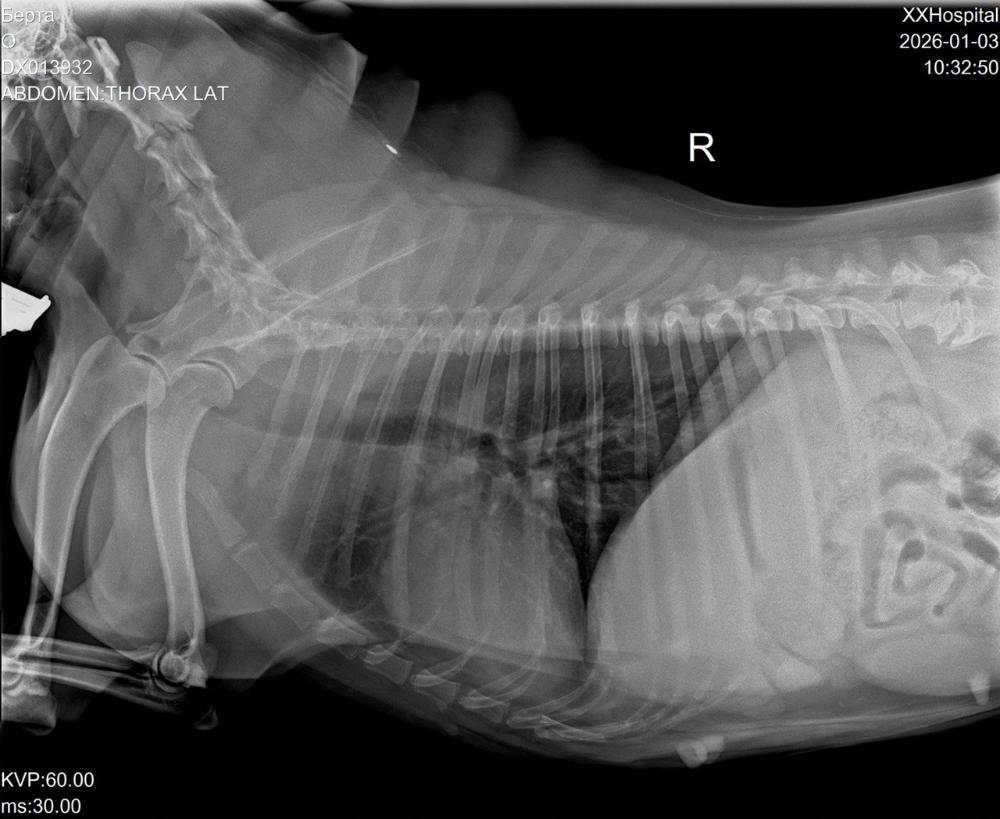

Вячеславовна Опубликовано 3 января Автор Опубликовано 3 января Добрый вечер!!! С'ездили сегодня с Бертой к кардиологу и пульманологу. По сердцу: расшифровка холтера неплохая, отменили ветмедин, через полгода пройти кардио обследование. Сдали ОКА и биохимию. Сделали рентген. ( результаты на почту). Тот кашель, который есть сейчас, не сердечный. Для диагностики кашля рекомендована ларинготрахеобронхоскопия(исключить изменение гортани, в тч ретро версию надгортанника, частичный паралич) и БАЛ. Всё это удовольствие на вес Берты стоит 30000р.🤔🧐🤔🧐 Подбор терапии по результатам обследования. Сейчас бромгексин 8 мг и ингаляции с физ раствором. Финансовый отчёт. Остаток: 15590р. Расходы: Пульманологу, рентген, анализы -8853р. Зоотакси -1330р. Остаток: 5407р. Помощь Берте очень актуальна!!! Мой номер 89261818009 привязан к карте СБ на имя Марина Вячеславовна М. с пометкой " Берта". 1